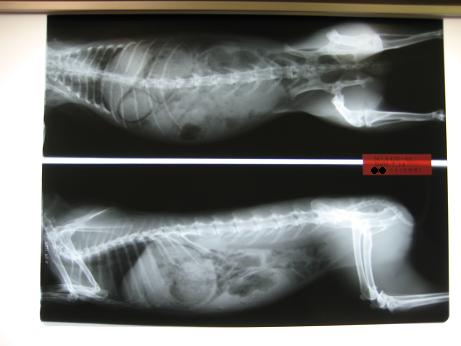

T先生『レントゲンでも肺も気管も正常ですし、考えられるのは

耳が熱ければ気温が暑い。それ以外でれば食べ過ぎで苦しい

のかも?ちょっとお腹にガスも溜まってるしなぁ。』

呼吸気管に問題があるのかな?とも思ったので今回はレントゲンも

胸中心に撮ってもらい、問題ない。と言われました。